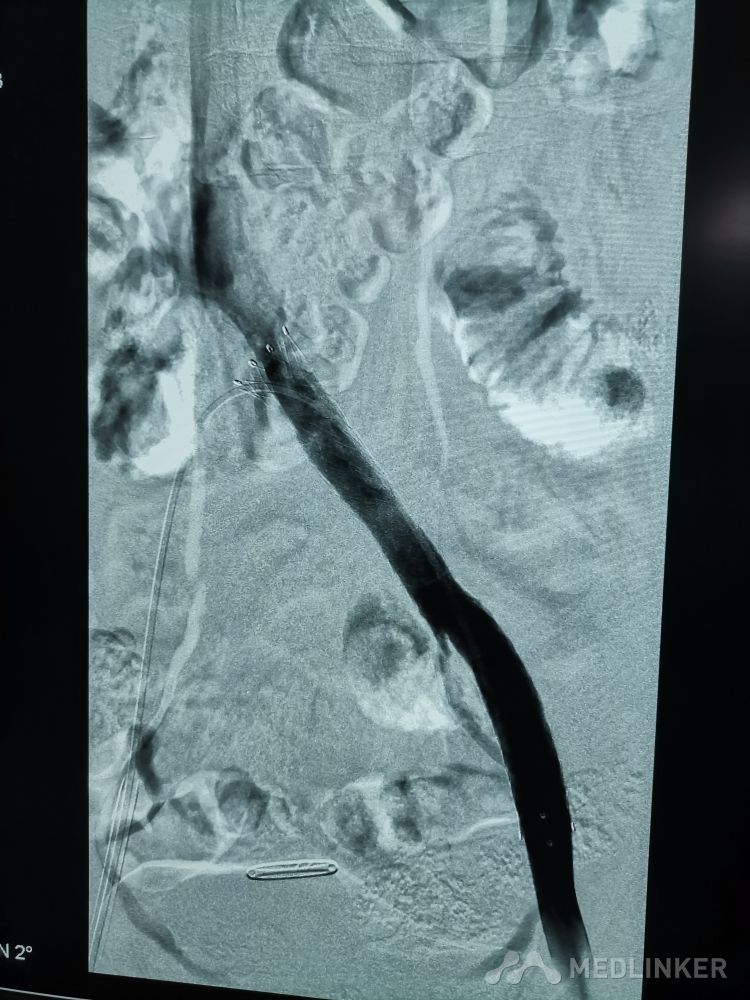

重视髂静脉压迫综合征。不同的临床表现,相同的病因,均为髂静脉压迫所致。第一例,表现为下肢静脉曲张伴溃疡,造影证实,髂静脉支架置入后解决。第二例,表现为左侧髂股静脉血栓,置管溶栓并髂静脉支架置入开通血管。第三例,下肢深静脉血栓后遗症,外院已行髂静脉支架置入,但皮肤营养情况仍持续加重,开通股浅 ,可见病变局部异常坚硬。精准施治,对症下药。